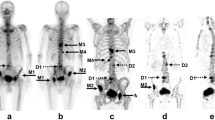

Figure 5 shows the results of serial BONENAVI and maximum intensity projection (MIP) images. PSA in Fig. 5b–d was significantly higher than that of the previous values, whereas ALP, BSI, and BMVI showed no obvious changes. Figure 5d, e seems to be almost identical with the extracted extent of bone metastasis, although the BMVI was higher than the BSI. Pelvic segmentation using the BONENAVI software showed overextraction below the ischial bone in all whole-body images (Fig. 5a–d) because of abnormal uptake of the right ischial bone. The abnormal uptake in the fifth lumbar vertebra was consistently interpreted by the physician as a degenerative change in all four bone scintigraphy. Extraction of the cervical spine in the MIP image (Fig. 5e) was also interpreted as a degenerative change.

Another patient showed results of serial BONENAVI and MIP images in Fig. 6. PSA and BMVI were rapidly elevated from Fig. 6b–e, and ALP was elevated after Fig. 6c. However, the BSI had a high value as shown in Fig. 6e. Furthermore, bone metastases in the bilateral ribs and right femur in Fig. 6c were interpreted by the physician and diagnosed as worsening compared with previous examinations. In Fig. 6b, a gradual progressive worsening of bone metastases in the thoracic and lumbar spine, ribs, and pelvis was diagnosed. The patient received chemotherapy and was then treated with Radium-223 (Fig. 6e).

The first step toward more accurate assessment of the extent of bone metastases in the entire skeleton should be accurate and reproducible measurement the skeletal volume. Since BSI calculation estimates the weight of each bone region segmented by part from the whole-body planar image and is the percentage of the weight of the entire skeleton and bone metastases, the segmentation accuracy is a pivotal factor [2]. The case in Fig. 5 showed that the pelvic segmentation was incorrect because of the overextraction of the ischial bone (Fig. 5a–d) and underextraction of the iliac bone (Fig. 5a, c). With our proposed method, the volume data of CT and SPECT images could be used to complement with each other, thus enabling the measurement of the entire skeletal volume with a lower variability of < 3%. This benefit has also been used to extract bone lesions. TBV is most strongly correlated with body weight (Fig. 2), a result that seems almost appropriate when estimated from the relative weights of each bone [23].

Another advantage of using SPECT/CT images to detect abnormal uptakes would be to avoid anatomical overlap. Lesion detection on whole-body planar images may not be accurate because of bone-on-bone overlap, and bone overlap in the kidneys, ureters, and bladder containing radioactive urine, as well as radioactivity contamination [25]. Patients with prostate cancer often have difficulty voiding properly. In Fig. 5, if an abnormal uptake was observed in the sacrum, no detection would have been possible, because of the radioactive urine in the bladder. Furthermore, in Fig. 5a, urine in the renal pelvis was detected as a less likely malignant uptake in the left rib. The region may not be accurately extracted even on curved rib contours (Fig. 6e). Moreover, planar images have lower contrast than SPECT images, which cannot be corrected for attenuation, scatter, and blurring because of collimator apertures.

The role of bone scintigraphy is very important because of its expected 10 year mortality rate of 90% if bone metastases are present at the initial diagnosis [14]. Unfortunately, the sensitivity and specificity of whole-body planar images are not that high, which may be improved by BONENAVI. Moreover, the survival risk of patients with prostate cancer classified by BSI could be clearly stratified [27, 28]. The sensitivity and specificity of BSI can be improved by classifying lesions as benign or malignant by physicians rather than by the fully automatic method; however, physicians’ subjectivity may cause interobserver variation in the BSI [14]. Furthermore, the lower the EOD grade of the patient, the lower the diagnostic accuracy of both BONENAVI and the physician. Many lesions may not be detected by BONENAVI as shown in Fig. 6. BMVISUV6 may allow early risk stratification of patients with lower BSI who show equivocal uptake on whole-body images. Just as BSI can be automatically calculated, TBV and the total MBV can also be automatically calculated using a freeware; therefore, BMVI can be obtained by simply dividing them. Our proposed method would also achieve a similar high agreement as BSI, because no observer subjectivity is required.